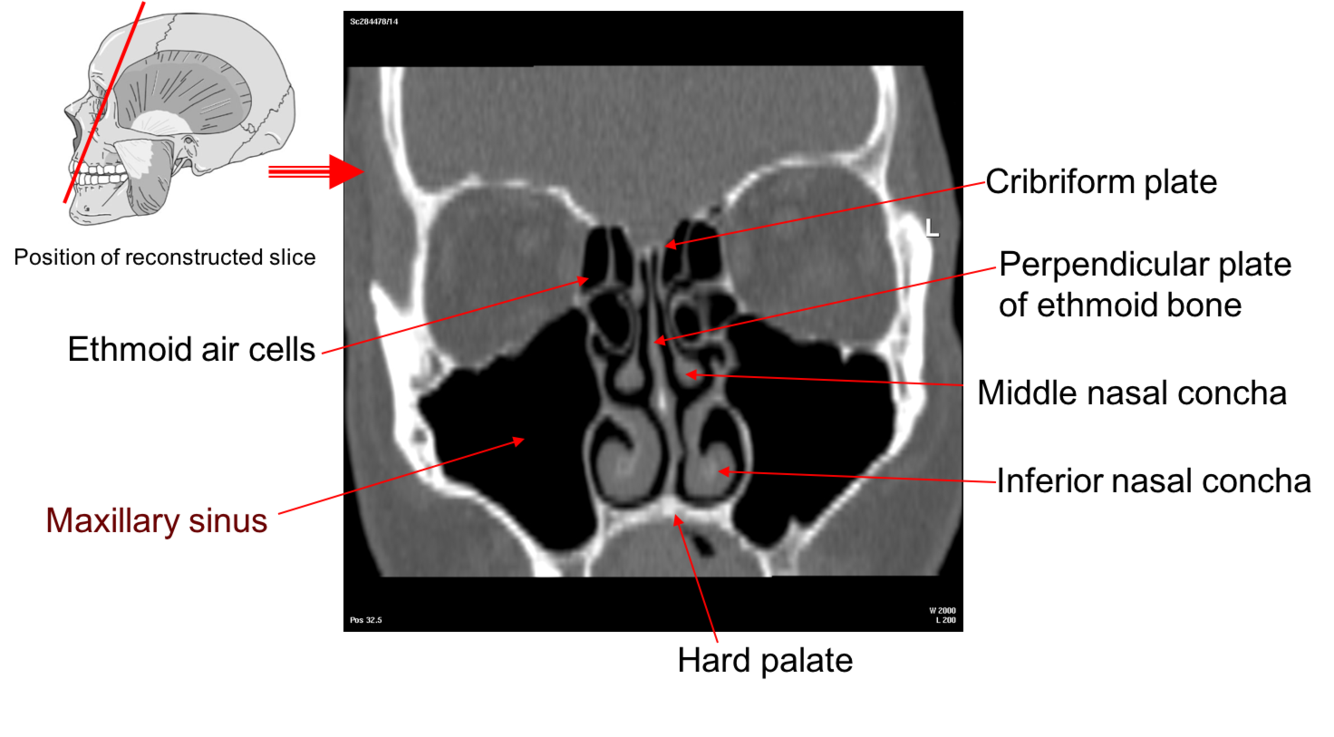

Label this image

The Nasal Conchae also called turbinates

These are thin scroll shaped bony plates that project into the nasal cavity. There are usually three the superior, middle and inferior nasal conchae (supreme may also be present).

•These conchae form passageways – the superior, middle and inferior meatae which are lined by mucous membrane

•This arrangement increases the surface area of the nasal cavities providing for rapid warming and humidification of air as it passes to the lungs.

The olfactory region of the nose is situated in the region of the superior nasal conchae. The olfactory bulb sits on the superior surface of the cribriform plate and cilia (hair like fibres) project through the plate to be suspended in the olfactory epithelium which is a section of the mucous membrane in the roof of the nasal cavity.